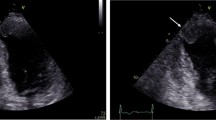

Among all the clinical variables that were entered into a univariate logistic regression analysis only two were significantly associated with outcome improvement in LVEF at follow up. The change in endocardial longitudinal strain (OR 1.2, 95% CI 1.03 to 1.42, P = 0.01) and the change in epicardial longitudinal strain (OR 1.2, 95% 1.03 to 1.46, P = 0.02) were significantly associated with the improvement in LVEF, independent of the location of STEMI and the presence of underlying multivessel disease (Figures 1, 2) (Table 5).

Panel A and B show attenuated global longitudinal endocardial strain in two patients with anterior wall myocardial infarction. Note the minimal improvement in longitudinal strain in the first patient (panel C) which has accompanied no improvement in LVEF. In contrast, panel D shows marked improvement in longitudinal strain on follow up in the second patient which is accompanied by significant improvement in LVEF.